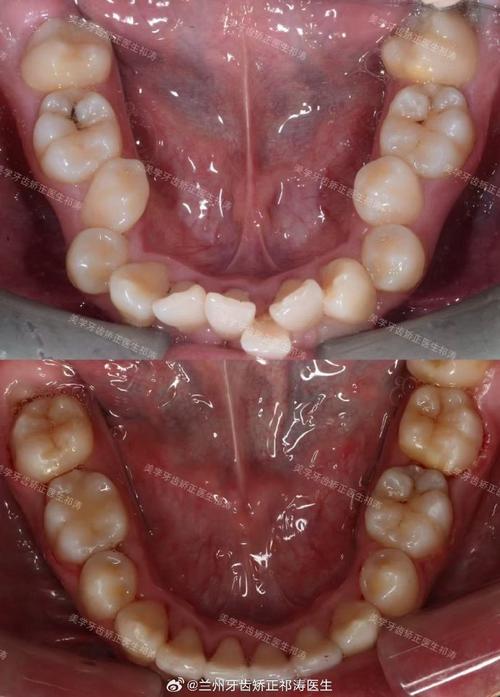

牙齿矫正的核心原理是利用生物力学,通过矫治器(如托槽、隐形牙套等)对牙齿施加持续、轻柔的力量,引导牙齿在牙槽骨中缓慢移动,在这一过程中,牙槽骨会发生“改建”:受压侧的牙槽骨逐渐吸收,受张力侧则新骨沉积,最终牙齿到达新位置,牙槽骨形态也随之重塑,这一原理为解决牙槽骨突出提供了理论基础——通过调整牙齿位置,带动牙槽骨改建,从而改善骨性突出,但需要注意的是,矫正对牙槽骨改建的影响是有限度的,对于轻中度的牙槽骨突出(尤其是牙齿唇倾导致的),单纯正畸矫正往往能取得良好效果;而对于重度骨性突出(如下颌后缩、上颌前突等),可能需要结合正颌手术,通过移动颌骨位置才能从根本上改善。

针对不同类型的牙槽骨突出,牙齿矫正需采取个性化方案,以常见的“牙齿唇倾型牙槽骨突出”为例,矫正目标是内收牙齿、减少唇倾度,从而带动牙槽骨向内改建,传统金属托槽矫正通过在牙齿上粘贴托槽,利用弓丝施加内收力,逐步将牙齿拉回牙槽骨中央;隐形矫正则通过一系列透明牙套,精准控制牙齿移动方向,同样实现牙齿内收,对于“骨发育型牙槽骨突出”,若患者处于生长发育期(如青少年),可通过功能性矫治器(如FRⅢ矫治器、 twin-block等)引导颌骨正常发育,抑制异常生长;对于成年患者,若骨性突出较轻,正畸矫正可通过调整牙齿代偿性移动(如下前牙唇倾、后牙伸长)来掩饰骨性缺陷;若突出严重,则需先通过正颌手术移动颌骨,再进行正畸精细调整,确保咬合关系稳定。